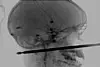

Røntgenbilde av Cunninghams skade. Utrolig nok gikk også denne ulykken bra. Foto: Medical News Network / AP

Røntgenbilde av Cunninghams skade. Utrolig nok gikk også denne ulykken bra.

Gutten, Xavier Cunningham, falt fra stigen til trehytten sin da han prøvde å unngå en sverm av veps, og falt ned på det 30 cm lange spydet.

Spydet boret inn til venstre for nesen hans, og nådde bakhodet hans – utrolig nok uten å treffe noen av hjernens sentrale deler.